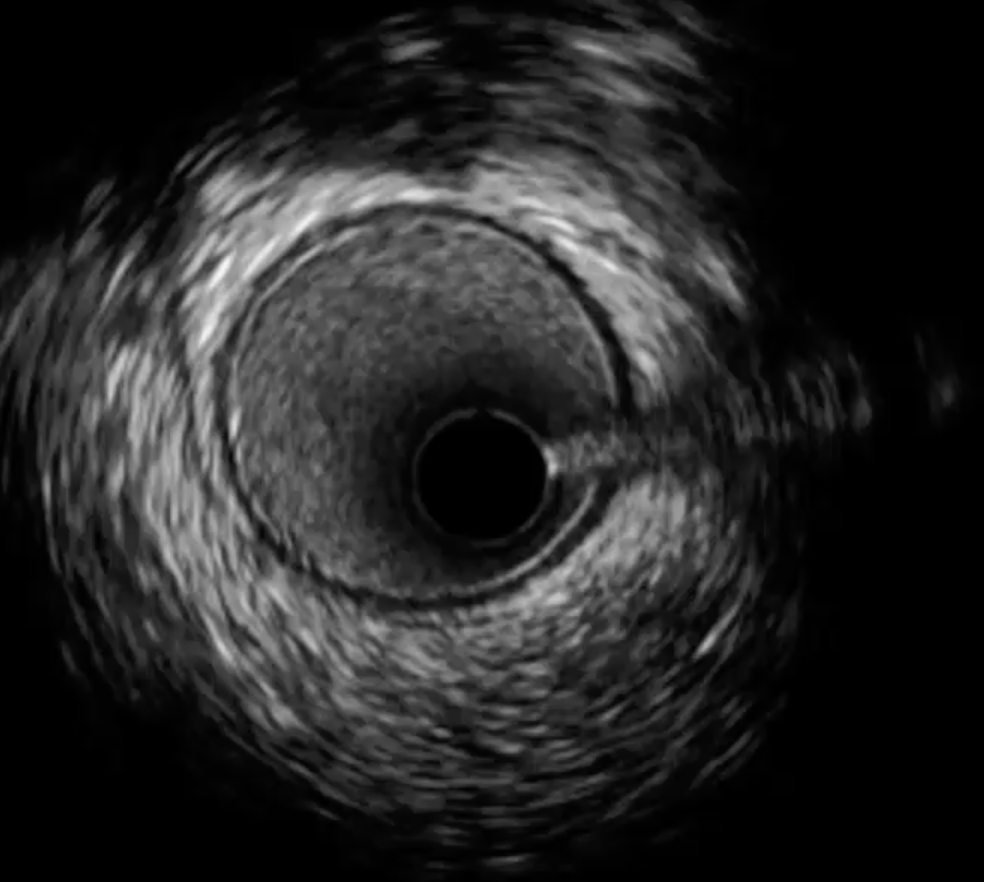

Q

What is shown here?

A

-Guidewire artefact